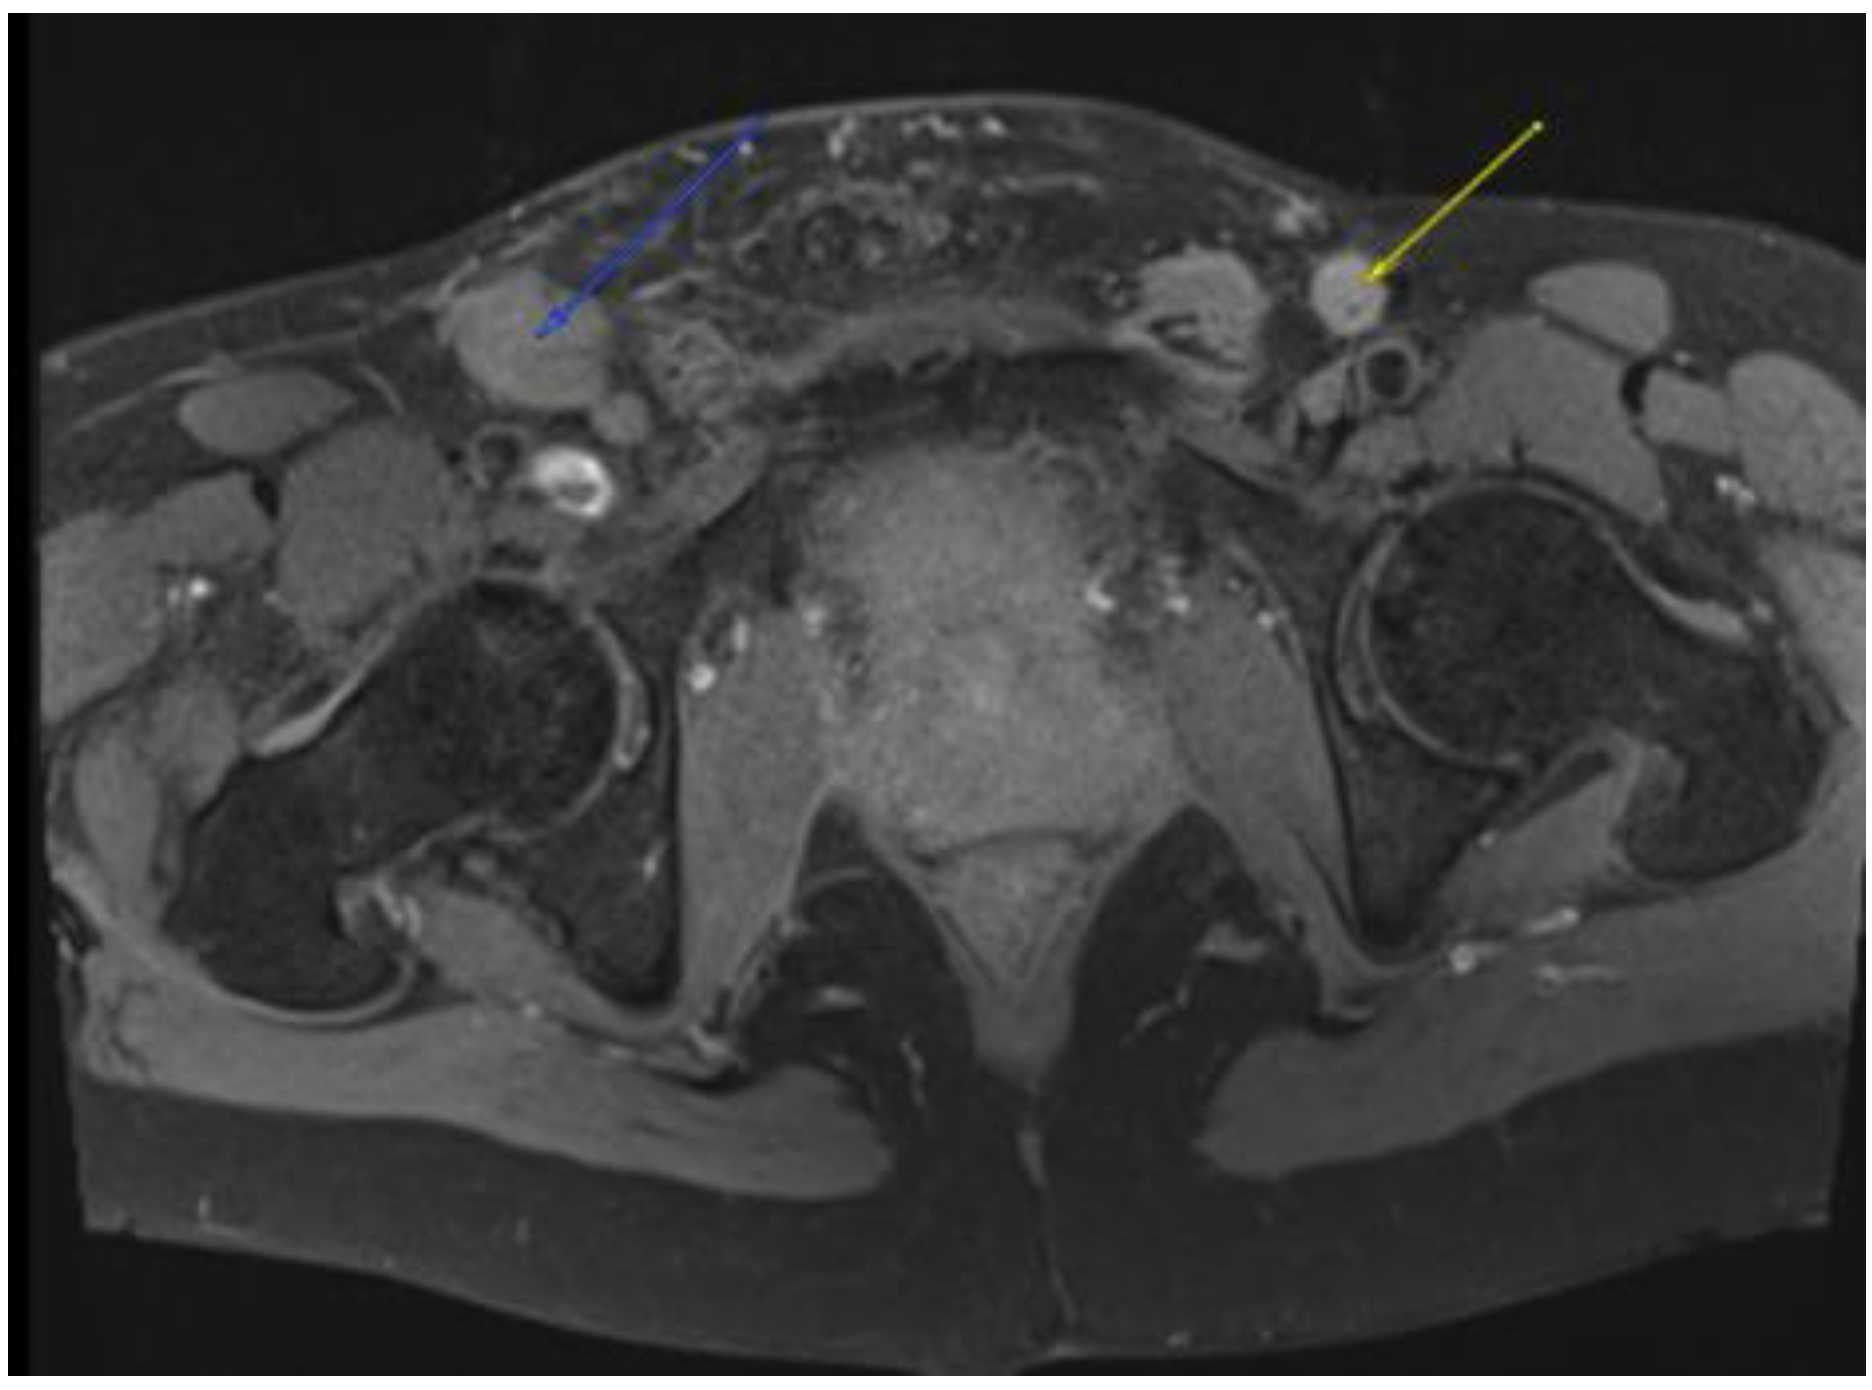

Figure 4.

MRI in the axial view T1 TSE FS pre-showing 11 mm R common iliac lymph node.